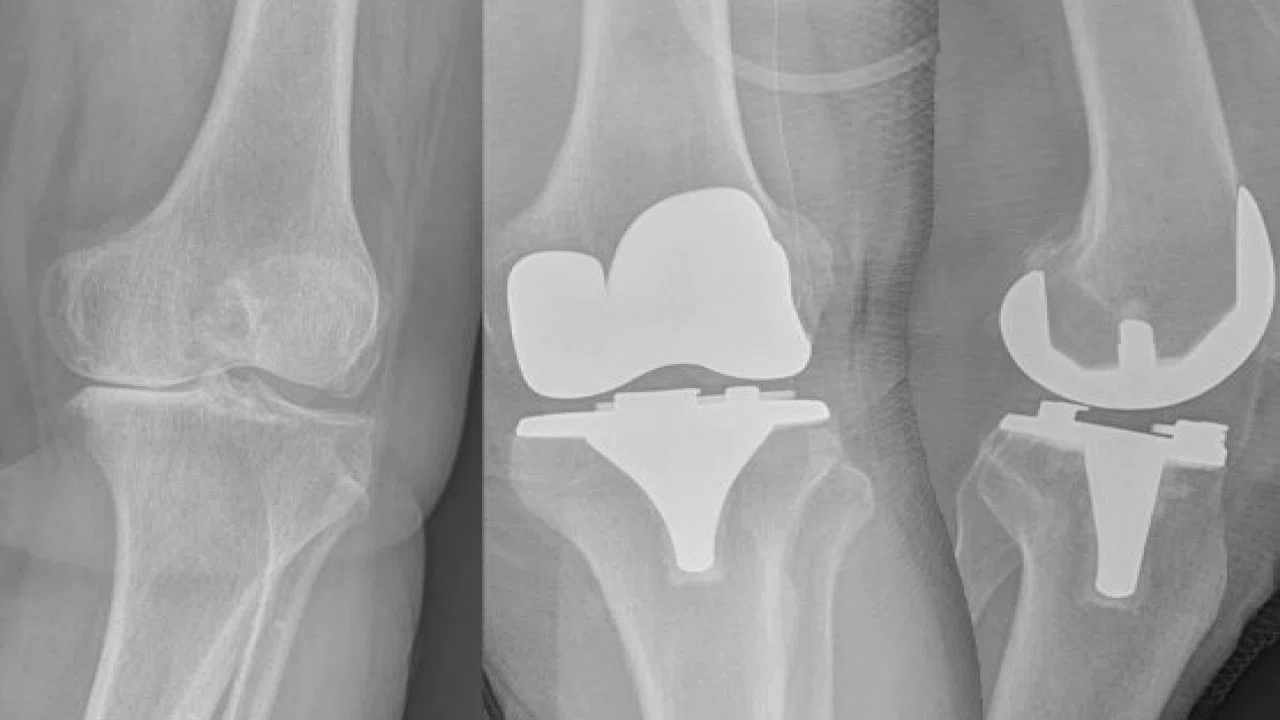

Röntgen filmleri, kemik ve dokuların görüntülerini oluşturmak için X-ışınları kullanır. Bebeklerin diz kapaklarında ise kemik yerine kıkırdak dokusu bulunur. Kıkırdak dokusu, X-ışınlarını kemik kadar yoğun emmediği için röntgen filminde görünmez.

Bebeklerin diz kapakları genellikle 3-4 yaşına kadar kemikleşmez. Bu yaştan önce diz kapakları röntgen filminde görünmese de, bu durum herhangi bir sağlık sorununa işaret etmez. Doktorlar, bebeğin diz eklemini değerlendirmek için diğer görüntüleme yöntemlerini kullanabilirler.